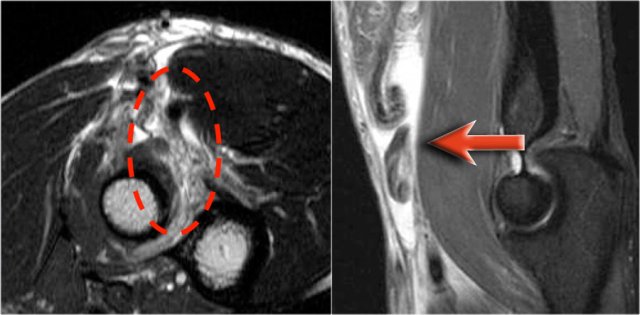

These images are of a 23 year old male who fell onto his outstretched hand two weeks ago while skateboarding.

On physical exam there was decreased range of motion of the elbow and tenderness along the lateral aspect.

What is the structure on the axial image behind the radial head?

Sagittal view:

• Again the characteristic pattern of marrow edema that is seen in posterior elbow dislocation with contusion in the anterior side of the radial head (red arrow) and on the posterior side of the capitellum.

• The radial head must have hit the posterior part of the capitellum.

The structure behind the radial head is the annular ligament.

It is irregular and thickened as a result of the posterior dislocation.